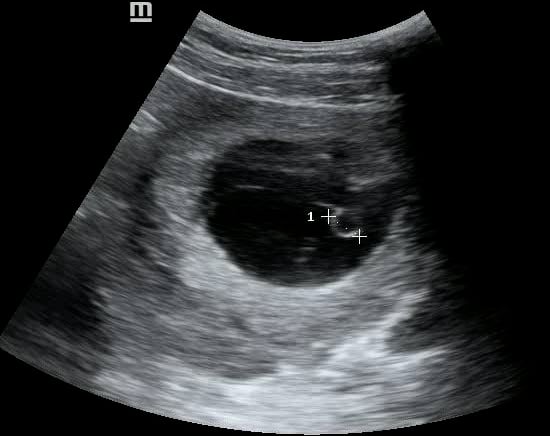

In OBGYN ultrasound, the yolk sac is a crucial early gestational structure, appearing as a small, round, anechoic fluid-filled sac within the chorionic cavity. Typically visible from 5-10 weeks of gestation, its presence confirms an intrauterine pregnancy and is a vital indicator of normal embryonic development. The yolk sac provides early nourishment to the embryo before the placenta fully forms.

Its proper visualization and size are important for dating the pregnancy and assessing viability. Abnormalities in yolk sac appearance, such as irregular shape or absent visualization when expected, can suggest potential complications or early pregnancy failure. Therefore, precise identification and evaluation of the yolk sac are fundamental for accurate diagnostic ultrasound in obstetrics.